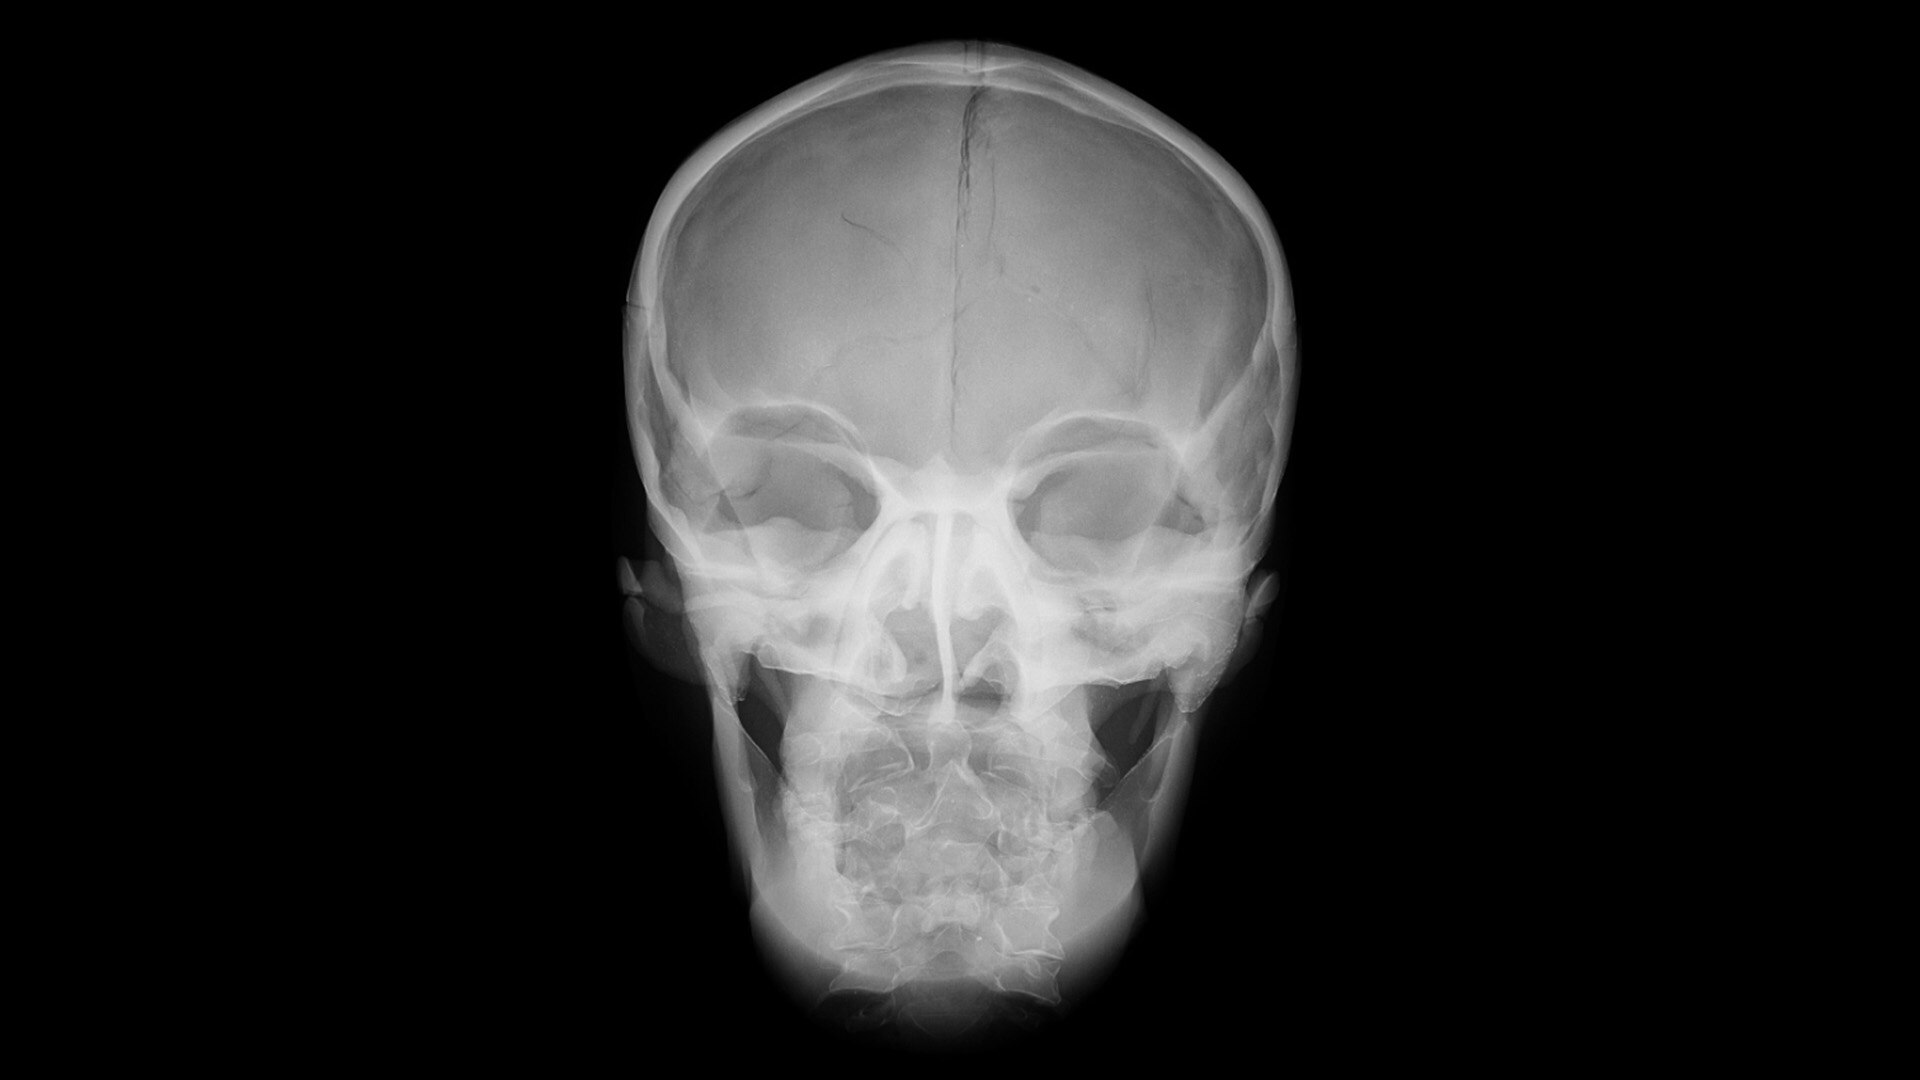

FETAL HEART EVALUATION

Get to the Heart of the Matter

Identifying fetal cardiac abnormalities earlier means you can intervene sooner, plan for delivery, and potentially improve outcomes. The Voluson Expert 22 provides a full solution of progressive tools, to help distinguish the tiniest structures with stunning clarity to provide patient answers faster.

Get high detail, high resolution 2D, 3D, and 4D imaging. Utilize easy automation to help obtain and visualize the recommended fetal heart or a complete exam.